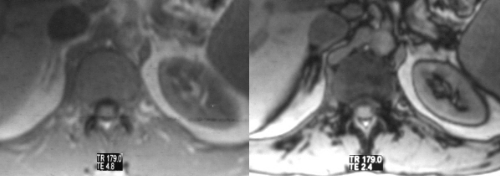

Because the normal adrenal gland is surrounded by retroperitoneal fat, the relatively low intensity of the gland is seen in sharp contrast to the fat, particularly on T1 weighted images. MRI is best used in the characterization of adrenal gland masses.The T1-weighted sequence is performed to optimize the morphology of the gland and the “in-phase” and “out-of-phase” techniques are also useful in defining the incidentaloma. The T2-weighted sequence enables the characterization of lesions with high water content as well as pheochromocytomas. |

These “in-phase” and “out-of-phase” T1-weighted images focus on the normal right gland. The left gland cannot be visualised on these images. On the “in-phase” sequence (first image), the adrenal is almost isointense with the liver while on the “out-of-phase” sequence, the gland darkens slightly. Courtesy of: Ashley Davidoff, M.D. |

These images reflect a normal right adrenal gland showing the difference between the normal T1-weighted and T-2weighted images. On T1-weighted images, (first figure) the intensity of the adrenals is almost isointense with the liver, while on T2-weighted image, (second figure) the adrenal is brighter than the liver. Courtesy of: Ashley Davidoff, M.D. |